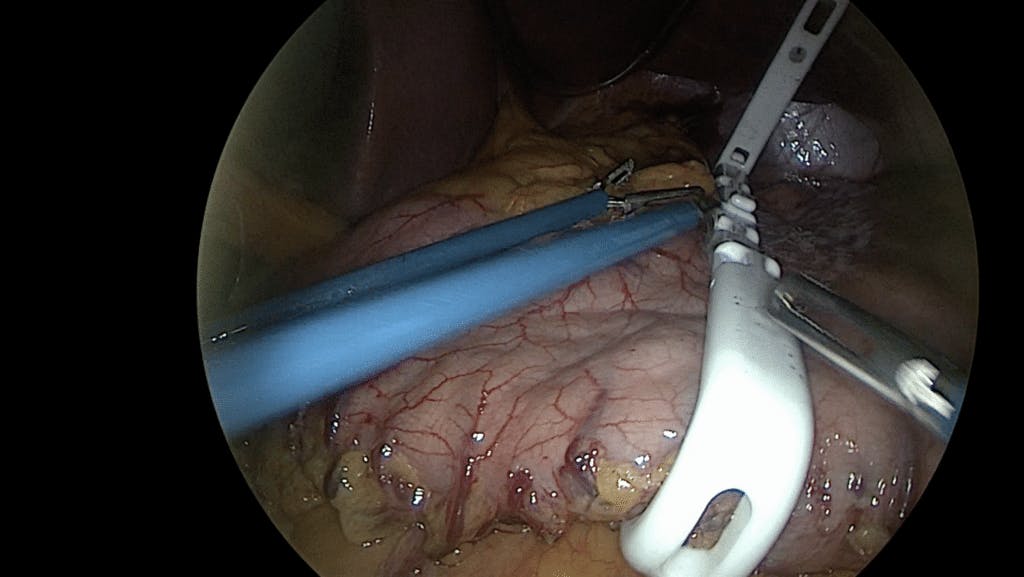

Laparoscopic BariClip – the procedure details

During the laparoscopic BariClip procedure, your bariatric surgeon creates small incisions along your stomach pouch before inserting the clip. Once placed, the device closes around the stomach to restrict its capacity. Finally, your surgeon sutures the BariClip in place. 27-29